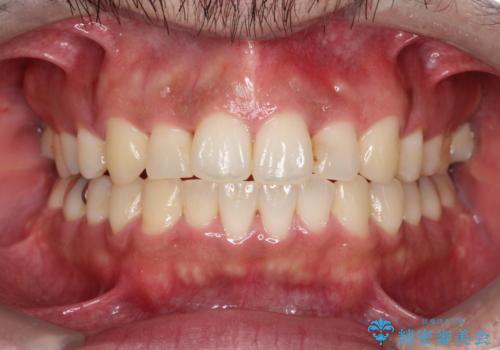

- 20代男性

- 出っ歯が気になるとのことで来院されました。

上顎の前から4番目の歯を両側、合計2本抜歯して矯正する計画としました。

目立たない装置がご希望でしたので、上下裏側ワイヤー装置を選択されました。